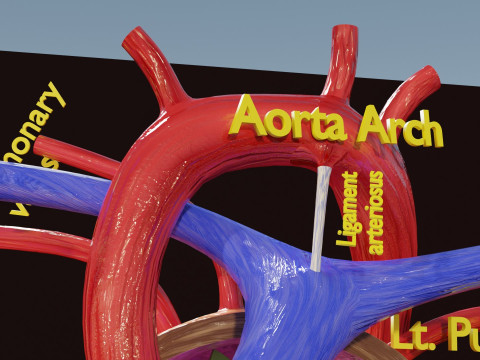

The model meshes include adult circulation versus circulation in Tetralogy of Fallot (TAF), arrow labels and text labels. The blood flow in a patient with Tetralogy of Fallot is outlined in this model. To contrast it to normal blood circulation a separate model of normal circulation is included. The Tetralogy of Fallot (OVER RIDING OF AORTA, PUL STENOSIS, VENTRICULAR SEPTAL DEFECT, RIGHT VENTRICULAR HYPERTROPHY), fossa, ligament teres , venosus, and arteriosus are duly depicted with proper labelling and blood flow directional arrows. Excellent model for teaching, demonstration and knowlegde of human body. The models include both procedural and image textures blend files separately. The texture file include diffuse, roughness and normal png and jpeg based on non overlapping UV maps.